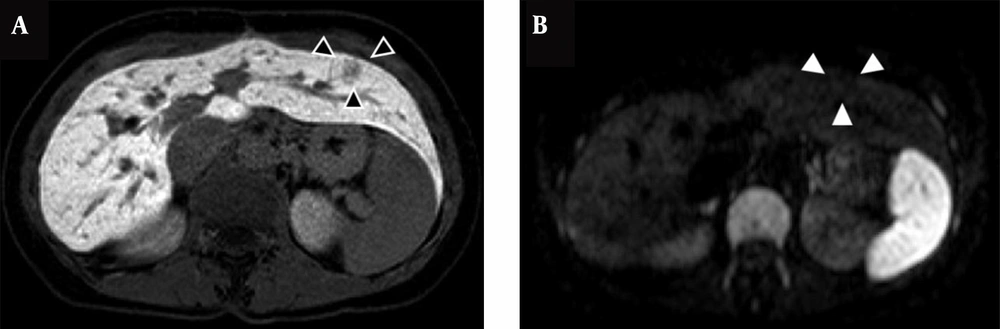

MRI revealed that the primary liver metastasis was a low-intensity mass on T1-weighted images and a high-intensity mass on T2-weighted images. The hepatocyte phase of Gd-EOB MRI and diffusion-weighted MRI clearly showed the mass to be a tumor. The pseudotumor by SOS also presented as a low-intensity mass on T1-weighted images (Figure 3A). However, the tumor was not detected by diffusion-weighted MRI (Figure 3B). This feature was confirmed on PET/CT. Therefore, the standardized uptake value of the pseudotumor was approximately equal to that of the liver parenchyma.